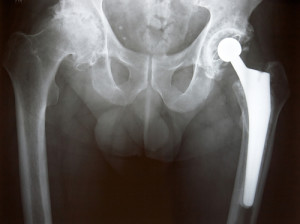

Con protesi d’anca si intende un intervento chirurgico che preveda la sostituzione dell’articolazione malata o fratturata con un impianto artificiale.

A seconda della frattura, dello stadio dell’artrosi, età e condizioni generali della persona, possono esser usati diversi modelli e materiali per la protesi. In particolare una delle principali distinzioni è tra protesi parziali o totali dell’anca.

Le protesi parziali d’anca, dette anche endoprotesi, sono usate più di frequente in caso di frattura di femore e consistono nella sostituzione dell’intera testa del femore con una protesi.

Le protesi totali invece, dette artroprotesi, sono più frequenti in casi di artrosi dell’anca e prevedono la sostituzione dell’intera articolazione.